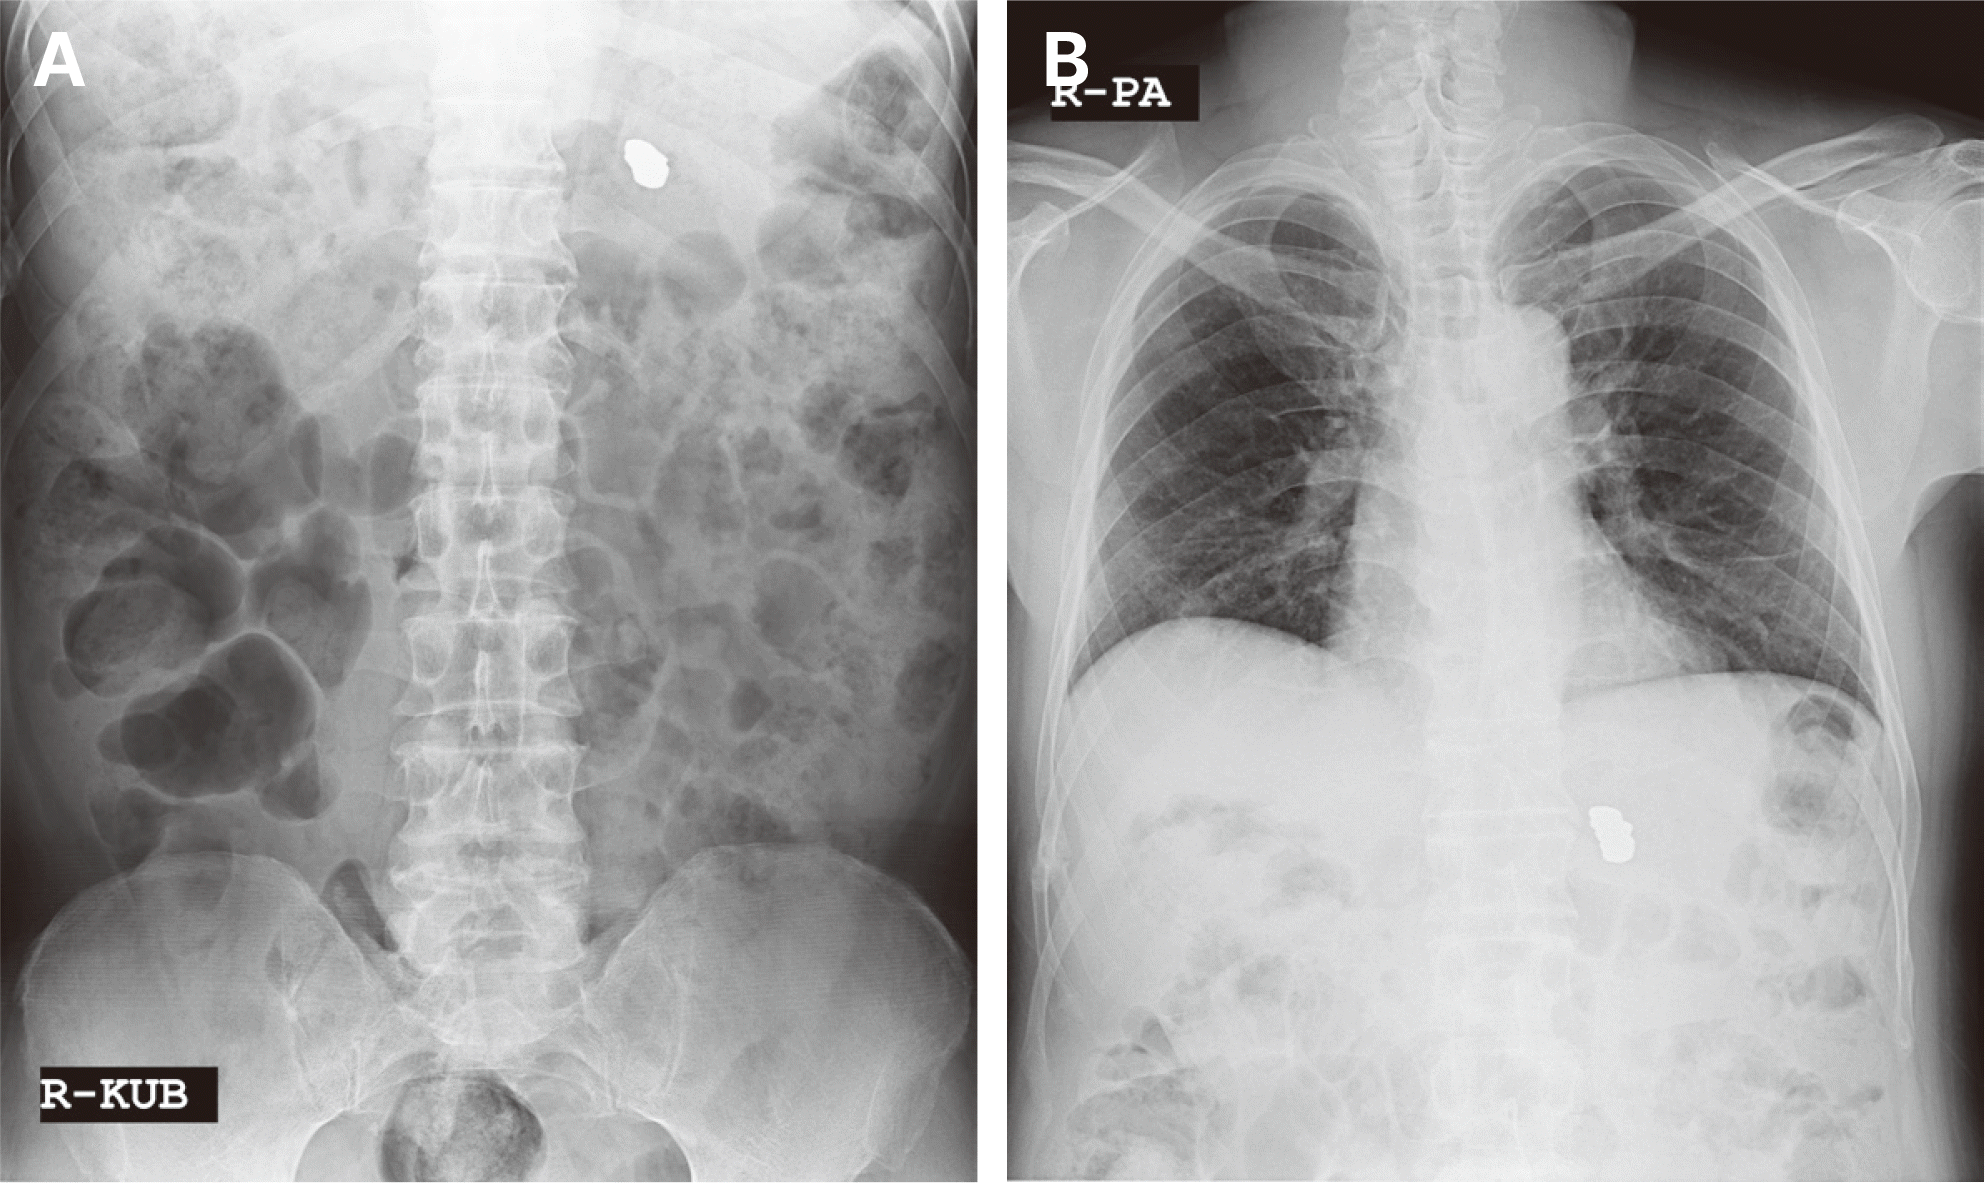

60세 남자 환자로 전체적인 치과치료를 위해 본원에 내원하였다. 환자는 의과적으로 기질성 정신장애를 진단을 받았으며, 거동이 불편하고 보행이 불가능하여 요양병원에서 입원 치료 중이었다. 정신건강의학과에서 환자의 정신장애에 대해 치료상태가 안정된 상태임을 확인한 후, 치과치료를 진행하였다. 파노라마 방사선 사진 및 구강검사에서 상악 우측 제1소구치와 제1대구치, 좌측 제제1, 2소구치, 하악 우측 제1대구치에 잔존 치근이 존재하였으며, 상악 우측 견치와 하악 좌측 견치 및 소구치에서 치아우식증이 관찰되었다(Fig. 1). 환자의 의과적 병력과 치료의 협조도, 구강위생 조절 능력 등을 고려했을 때, 가철성 보철물의 유지와 관리가 어렵다고 판단되어 고정성 보철물로 수복을 계획하였다. 예후가 불량한 상악 우측 견치, 제1소구치, 제1대구치와 좌측 제제1, 2소구치, 하악 좌측 견치, 제1소구치와 우측 1대구치를 발치 한 후, 치아 상실부위에 임플란트 식립을 하였고(Fig. 2), 골유착 기간을 거쳐 최종인상을 채득하였다. 제작한 임플란트 보철물을 장착하던 과정에서 치과의사는 하악 우측 제제1, 2소구치와 제1대구치로 이루어진 3본 지르코니아 보철물이 환자의 구강 내로 떨어뜨렸고, 떨어진 즉시 환자의 두부를 좌측으로 돌려 환자가 보철물을 삼키지 않도록 노력하였으나, 환자가 보철물을 삼키게 되었다. 환자가 보철물을 삼킨 이후 기침이나 구토 반사 등의 특이적 소견을 보이지 않았으며, 호흡상태는 양호하였다. 환자 보호자에게 보철물 장착과정에서 보철물을 구강 내로 떨어뜨렸고, 이후 삼킴이 발생하였음을 설명하였다. 그리고 삼켜진 보철물의 위치 확인을 위하여 인근 내과로 전원 의뢰를 시행하였다. 전원 의뢰된 당일, 내과에서 복부 방사선 사진을 촬영하였고, 판독 결과 보철물이 위장에 위치를 하고 있음을 확인하였다. 24시간 이후 배출될 것으로 예상되어 48시간 후 재촬영이 필요할 것이라는 회신서를 확인하였다(Fig. 3). 2일 후 환자를 내원하도록 하여 추가로 복부 방사선 사진을 촬영하였다. 방사선 사진에서 위장관 내에서 보철물 확인되었다. 환자의 거동이 불편하여 위장관 운동이 저하되어 있는 상태이기 때문에 배출이 지연될 수 있다는 의과적 소견을 회신 받았다(Fig. 4). 8일 후 환자의 복부 방사선 사진을 촬영하였으며, 보철물이 위장관에서 완전히 배출되어 체 내에 있지 않음을 확인하였다(Fig. 5). 이 후 하악 우측 제1, 2소구치와 제1대구치에 새로운 보철물을 제작하여 최종 합착(Rely-X, 3M ESPE, St Paul, USA)을 시행하였다(Fig. 6).

59세 여자 환자로 심한 치주염으로 예후가 불량한 하악 우측 제2대구치 발치 및 임플란트 식립을 위해 본원에 내원하였다(Fig. 7). 하악 우측 제2대구치를 발치하고 임플란트 식립하였다(Fig. 8). 골유착기간을 기간을 거쳐 임플란트 최종인상을 채득하였다. 하악 우측 제2대구치 임플란트 부위에 맞춤 지대주와 상부 임시 치관을 장착하였고, 적응도를 평가하기 위해 경과 관찰을 시행하였다. 4일 후 환자가 상부 임시 치관을 분실하였다고 내원하였다. 환자는 식사 시에 임시치관이 탈락한 느낌이 없었으며, 기상 시에 갑자기 없는 것을 확인한 것으로 보아 취침 중에 삼킨 것 같다고 하였다. 단일 임시 치관의 형태와 크기, 방사선 불투과성에 대해서 설명하였고, 삼켰을 경우 나타날 수 있는 합병증의 가능성을 설명한 후, 인근 내과로 전원 의뢰하였다. 내과에서 촬영한 복부 방사선 사진에서 임시치관을 관찰할 수 없었으며(Fig. 9), 임시치관 재료의 방사선 불투과성으로 인해 나타나지 않을 수도 있음을 추가로 설명하였다. 환자에게 일주일 정도의 경과 관찰이 필요함을 설명하였고, 그 기간 동안 특이 소견이 없음을 확인하였다. 이 후 최종 보철물을 제작하여 합착(Rely-X, 3M ESPE)을 시행하였다(Fig. 10).